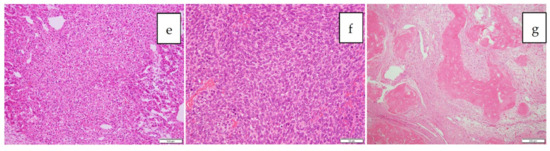

| 1 | 1 | 1y/F | PDE 1 neo system | left lobectomy | mixed epithelial and mesenchymal type with teratoid features, post-chemotherapy | uneven | 125 × 75 × 70 mm | 87.8 | identification, surgical margin, 20 m |

| 2 | 2 | 2y/M | PDE neo system | LDLT 2 | combined fetal and embryonal subtype, post-chemotherapy | uneven | 40 mm, 70 mm | 5514.4 | identification, surgical margin, 29 m |

| 3 | 3 | 8m/M | PDE neo system | right lobectomy | fetal, post-chemotherapy | uneven | 65 mm | 41,311 | identification, surgical margin, 18 m |

| 4 | 4 | 1y/F | PDE neo system | right trisegmentectomy | combined fetal and embryonal subtype, post-chemotherapy | uneven | 65 mm | 936.3 | identification, surgical margin, 17 m |

| 5 | 5 | 4y/M | PDE neo system | LDLT 2 | combined fetal and embryonal subtype, post-chemotherapy | uneven | 90 mm | 42591 | identification, surgical margin, newly detected tumors, 19 m |

| 6 | 6 | 2y/M | PDE neo system | LDLT 2 | embryonal, post-chemotherapy | uneven | 25 mm, 10 mm | 6.6 | identification, surgical margin, not disease free |

| 7 | 7 | 9m/M | PDE neo system | left lobectomy | mixed fetal and embryonal subtype, post-chemotherapy | uneven | 51 × 66 × 52 mm | 46.1 | identification, surgical margin, 3 m |

| 8 | 8 | 14y/M | PDE neo system | partial resection (recurrences in the transplanted liver) | wholly epithelial type and fetal subtype | diffuse | 8 mm | 69 | identification, surgical margin, newly detected tumors |

| 9 | 8 | 14y/M | PDE neo system | LDLT 2 | wholly epithelial type and fetal subtype | diffuse | 8 mm | 394 | identification, surgical margin, 34 m |

| 10 | 9 | 8m/F | PDE neo system | right lobectomy | mixed epithelial and mesenchymal, post-chemotherapy | uneven | 22 × 17 mm | 1340 | identification, surgical margin, 26 m |

| 11 | 10 | 1y/M | PDE neo system | right lobectomy | fetal, post-chemotherapy | uneven | 128 × 88 × 70 mm | 807 | identification, surgical margin, 7 m |

| 12 | 11 | 1y/M | PDE neo system | left lateral segmentectomy | fetal | uneven | 32 × 25 × 20 mm | 361.5 | identification, surgical margin, 1 m |

| 13 | 12 | 4y/M | PDE neo system | LDLT 2 | mixed epithelial and mesenchymal, post-chemotherapy | uneven | 130 × 115 × 90 mm | 545323 | identification, surgical margin, false positive, 8 m |